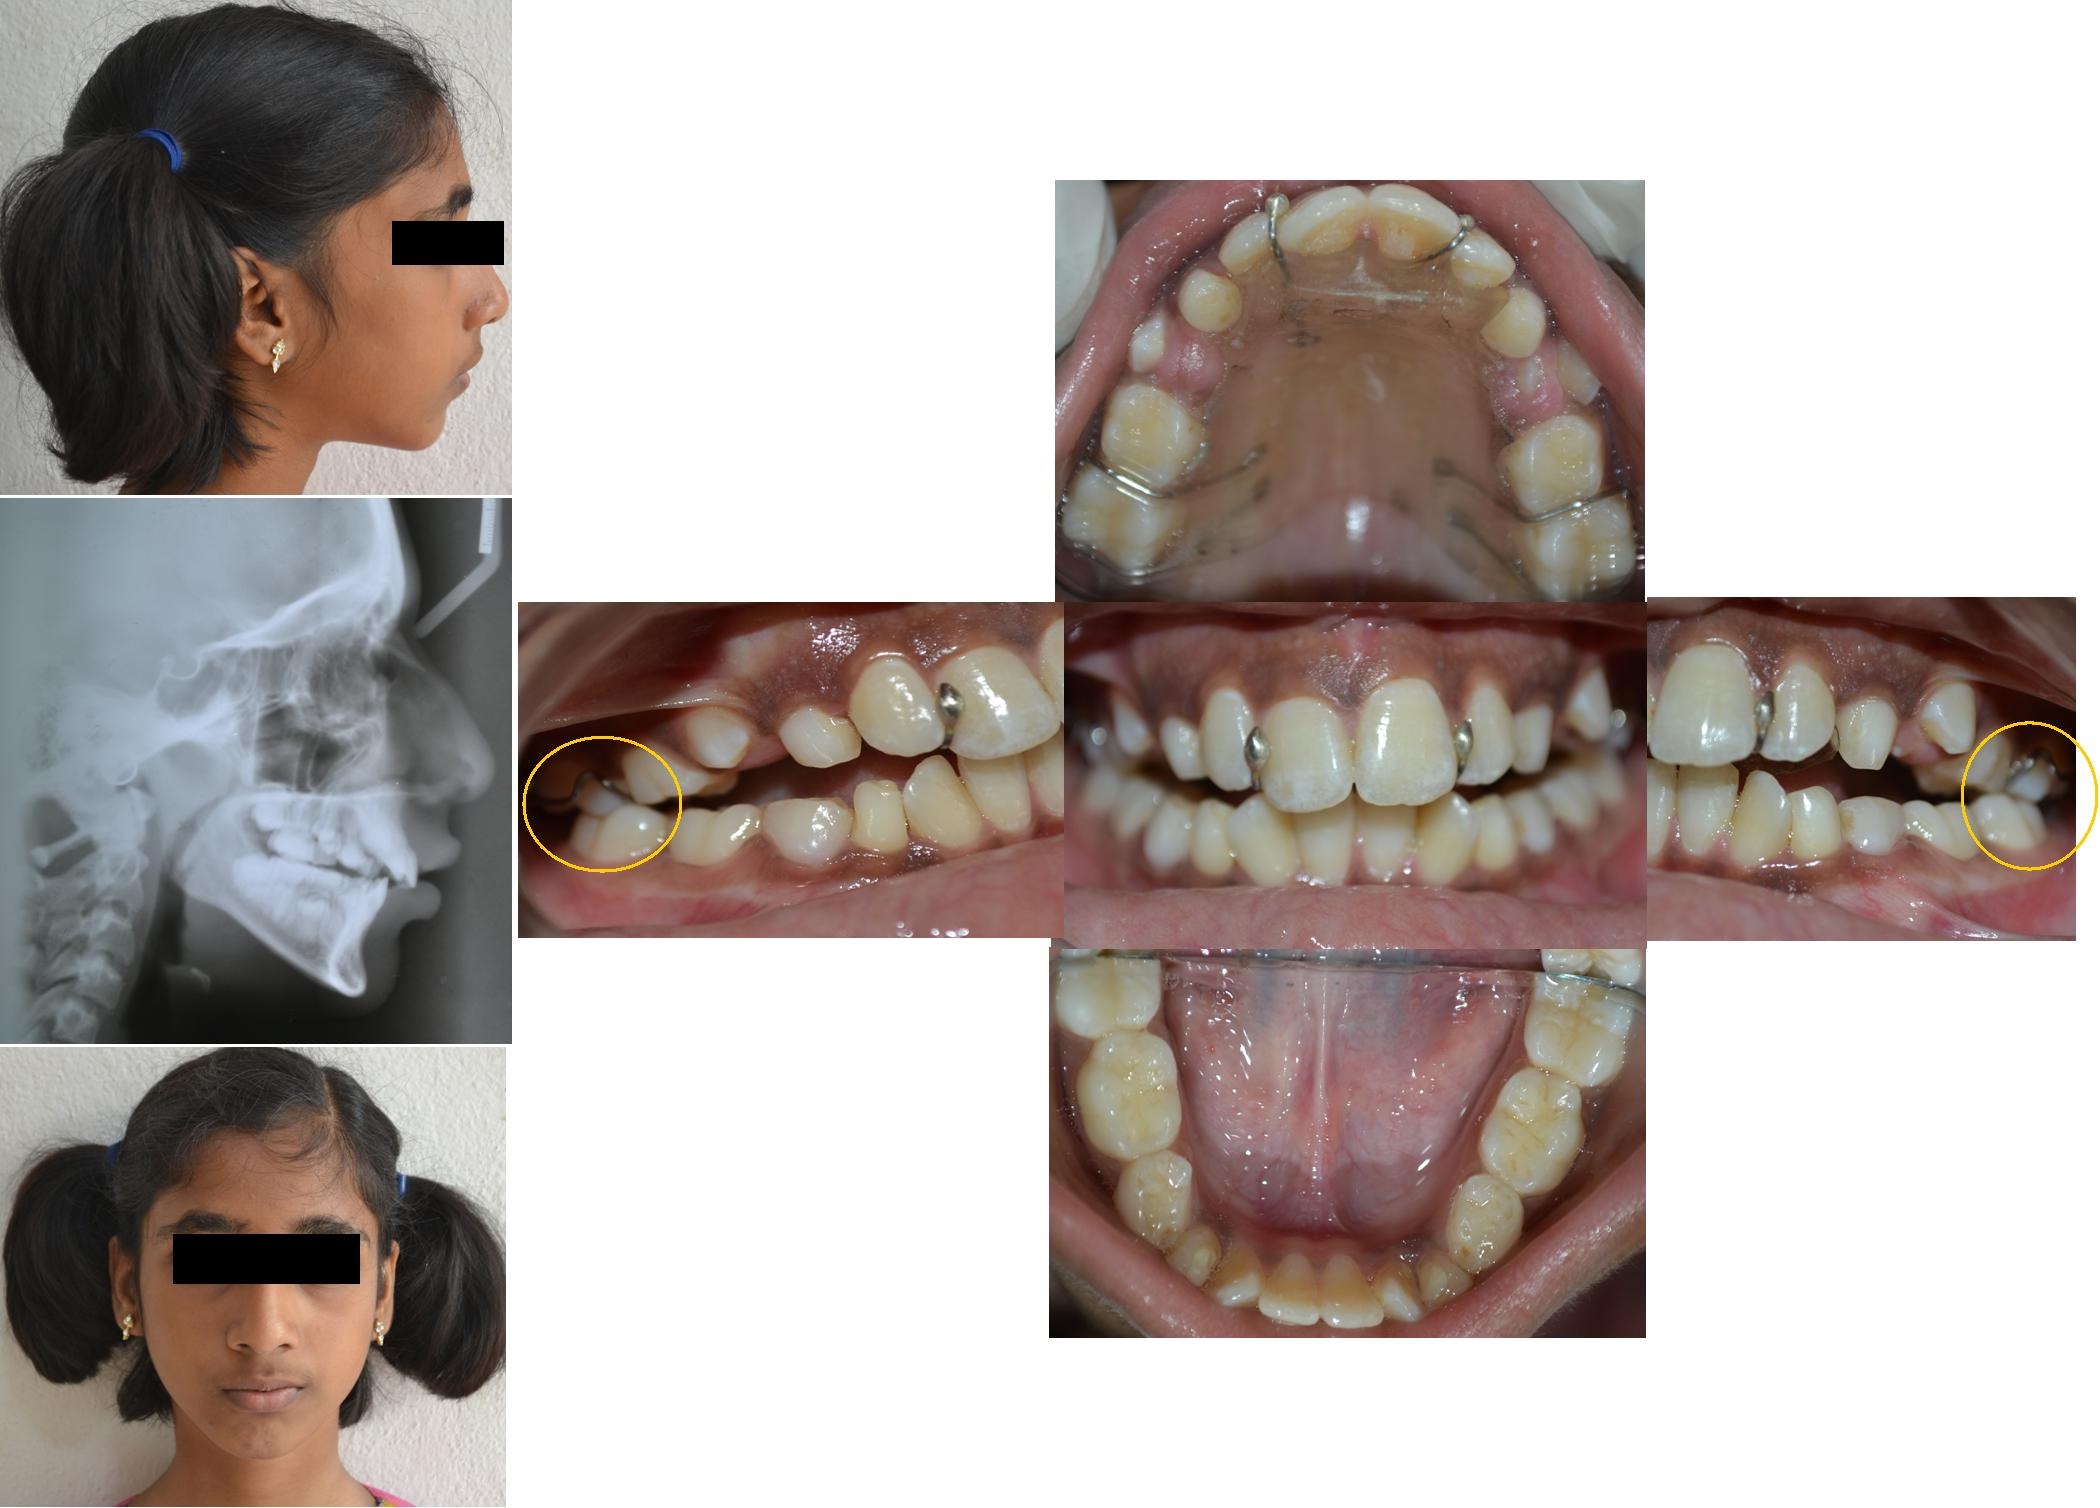

A 10-year-old female patient accompanied by her mother reported to the Department of Pedodontics and Preventive Dentistry with the chief complaint of unaesthetic appearance and irregularly placed upper front teeth. Clinical examination revealed the following features: Convex facial profile, incompetent lips and lower lip trap. On intra-oral examination, she presented a mixed dentition stage, labially placed 12, 21, disto-palatal rotation of 11, mesio-labial rotation of 32, 42, V-shaped maxillary arch. The patient exhibited an increased overbite, overjet, midline shift towards the patients right side and end on molar relationship on both sides [Table/Fig-1]. The patient’s medical and family history was non-contributory.

Pre-treatment extra and intra-oral photographs.